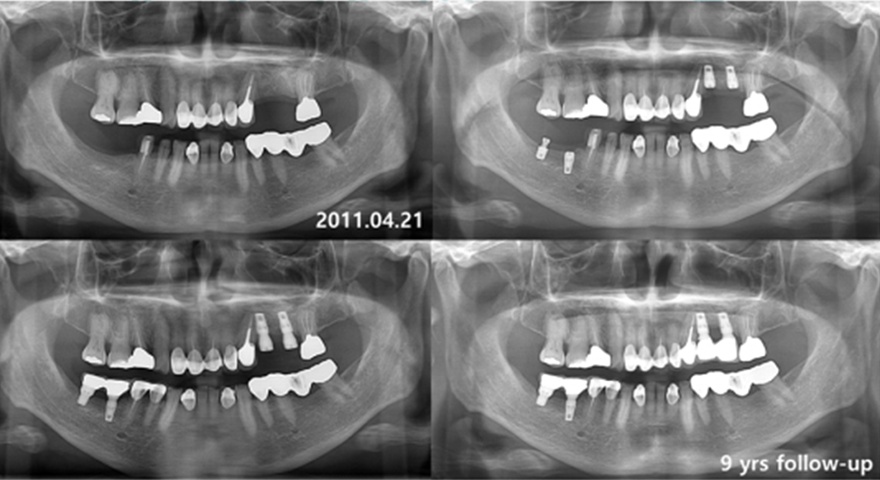

віддалені результати встановлленя короткого імплантату INNO Sub. Short

дані спостережень 8-10 років